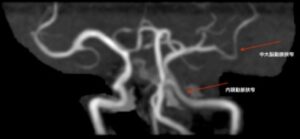

実際には、MRIと同時に撮影されたMRAでは、左中大脳動脈のM1〜2及び左内頸動脈に狭窄が認められていました。ABCD3-Ⅰスコアにおいては、同側内頸動脈(Aさんの症状は右上下肢麻痺でしたのでこれに該当します)の50%以上狭窄が+2と評価されることになっており、本当は注目すべきサインなのですが、B病院の主治医はこれを全く認識していませんでした。